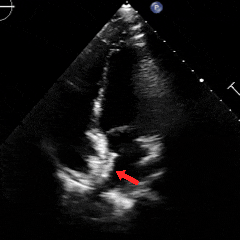

经胸右心声学造影:经左肘静脉注入震荡生理盐水(8mL生理盐水+1mL回抽静脉血+1mL空气经震荡制成),上腔、右房依次显影,造影剂完全充盈右心后,平静呼吸时,左房内即可探及微泡回声,约20-30个/切面/帧;瓦氏呼吸释放即刻,左房内探及微泡回声,不可计数。

术前静息状态经胸右心声学造影(中量)

术前瓦氏动作后经胸右心声学造影(大量)